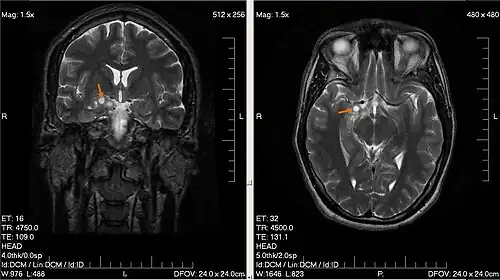

![]() Опухоль головного мозга. Визуализируется с помощью МРТ. | |